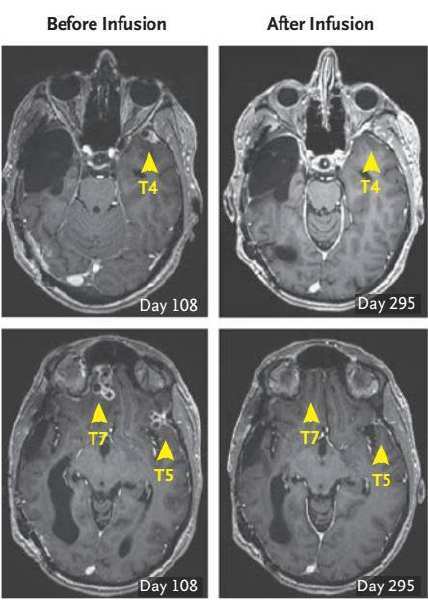

传统治疗效果不理想,于是走投无路的Richard加入了City of Hope癌症研究中心的I期临床研究中。研究人员通过MRI定位了Richard脑部的5个进展性颅内病灶,包括通过手术切除的三个病灶,分别是横跨右侧颞叶与枕叶最大个的T1和右侧额叶的T2和T3,及未经手术切除的左侧颞叶T4和T5小病灶。研究者还监测出Richard体内的 IL13Rα2蛋白表达在不同的肿瘤组织表达不均匀,但原发和复发的肿瘤细胞均显示IL13Rα2阳性。

经过3次注射后(挡急治疗第133天),研究者惊喜地发现所有颅内及脊柱内的肿瘤都在缩小,缩小幅度高达77%!在第5次注射(治疗第190天)时,word哥,所有的肿瘤都消失了!

当然药不能停,Richard后续又接受了5次注射治疗。在巩固治疗阶段,所有肿瘤继续分解,已经无法从MRI或是PET-CT检查中辨认出了。更神奇的是,在进行颅内IL13Rα2-CAR T细胞注射后,脊柱中的两处转移灶也完全被移除。在治疗的108天至284天中,Richard都未系统性服用地塞米松,也由此回到了他最爱的亲人和朋友身边,继续正常的生活。

治疗后的7.5个月里,没有任何一个原始肿瘤(T1-7)复发。然而可惜的是,在治疗后的地228天,Richard脑中终于又出现了四处新发病灶。

不过,新肿瘤与前7个肿瘤灶并不相邻,甚至相隔甚远。这也表明CAR-T疗法仍然对注射区域存留一定影响。回想起第一次治疗远隔肿瘤灶(T4-T7)的不理想,这个结果或许“有迹可循”。目前,真正的复发原因仍在调查之中,不过已有初步结果显示,IL13Rα2的表达量确实减少了。